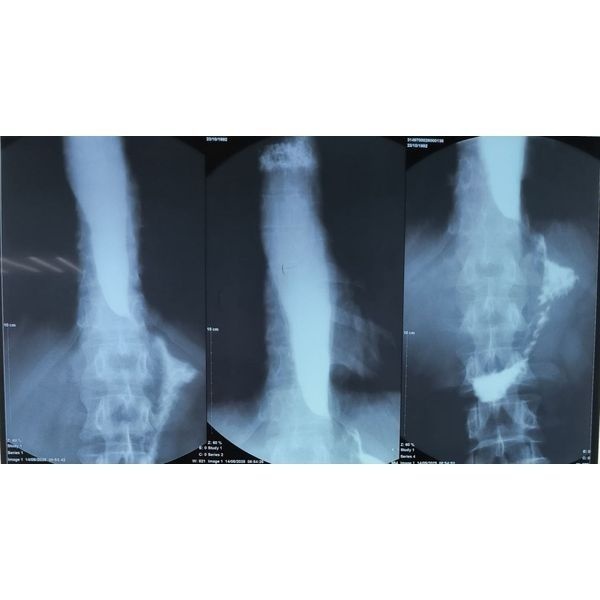

В ходе рентгеноскопии пищевода и желудка с контрастным веществом выявлено, что дистальный отдел пищевода (нижняя часть, примыкающая к желудку) сужен по типу хвоста мыши, что указывает на ахалазию кардии (нарушение работы клапана между пищеводом и желудком). Над этим участком пищевод умеренно расширен без S-образной деформации, т. е. он не удлинился и не искривился.